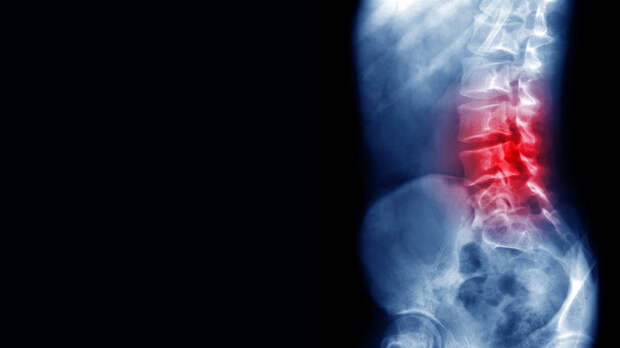

Врач-невролог, эксперт телеканала «Доктор» Павел Бранд рассказал, что боли в спине по ночам являются тревожным сигналом.

В беседе с сайтом kp.ru эксперт отметил, что следует серьёзно отнестись к ситуациям, когда боль возникла при отсутствии недавних травм, а также усиливается в положении лёжа, сопровождается повышением температуры.

По словам специалиста, особое внимание стоит обратить на боли у детей, подростков и людей старше 55 лет.